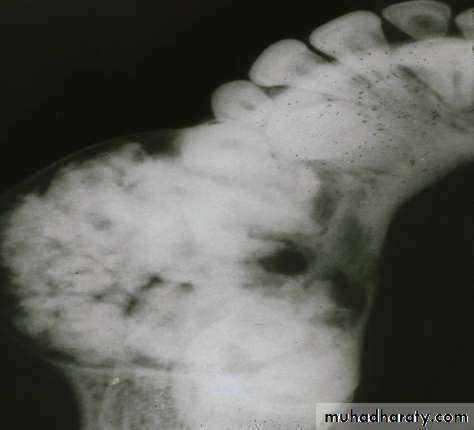

• Radiography:• Uni or Multilocular radiolucent areas

• Soap bubbles

• Copyright 2003, Elsevier Science (USA). All rights reserved.• Ameloblastoma

• Radiography:

• Soap bubbles appearance